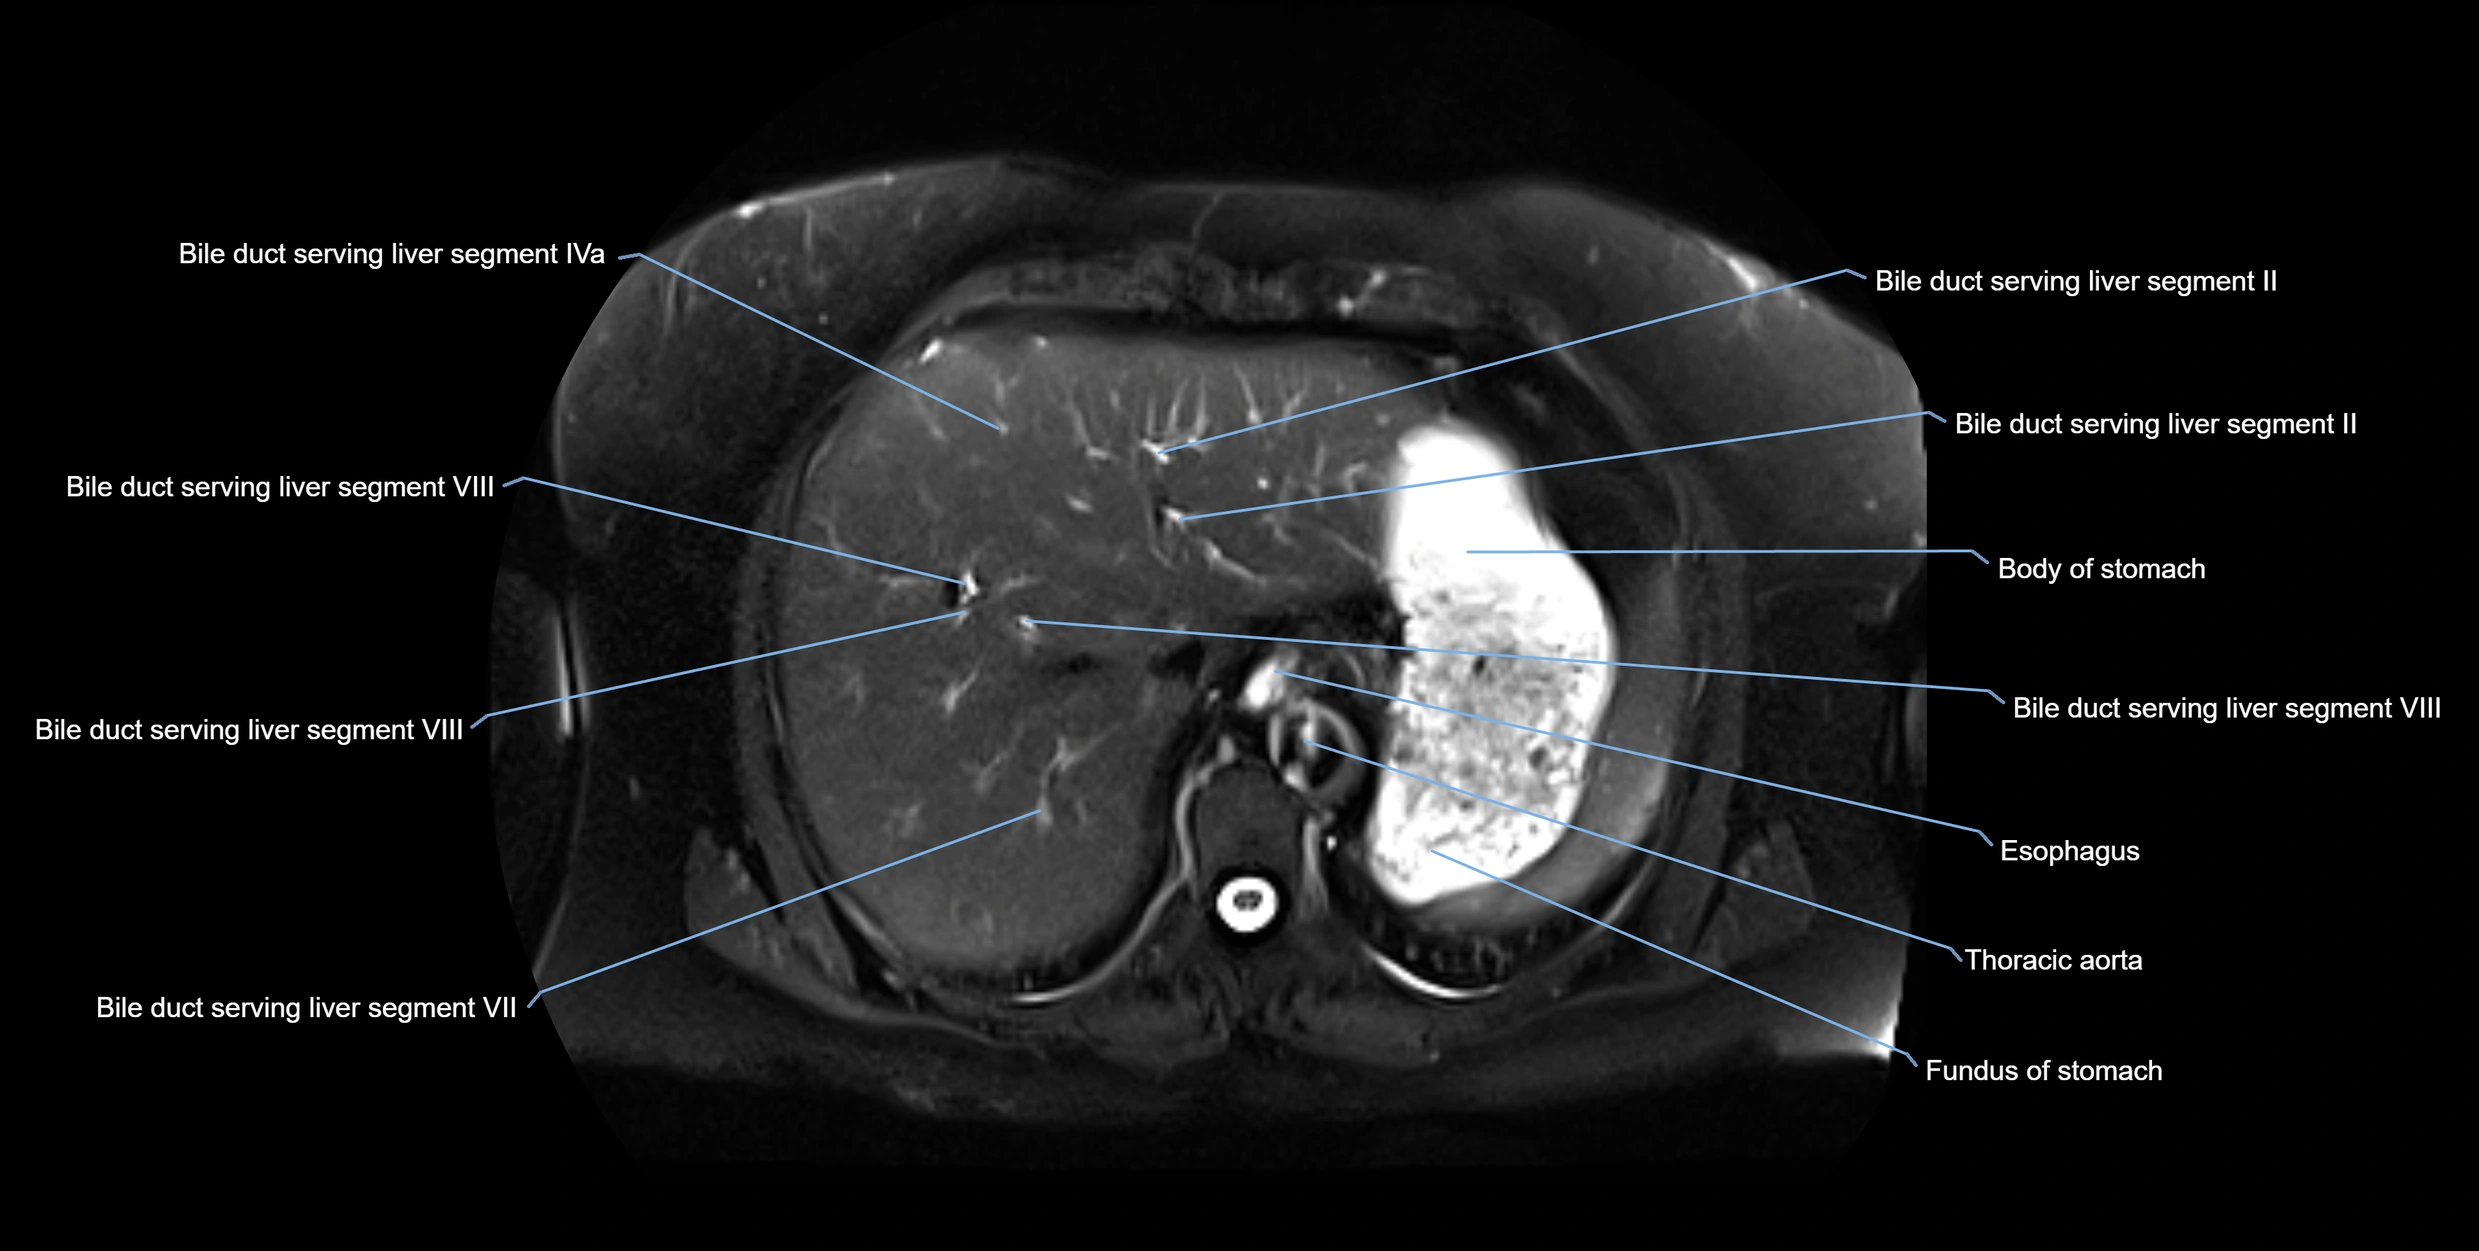

MRI image

image